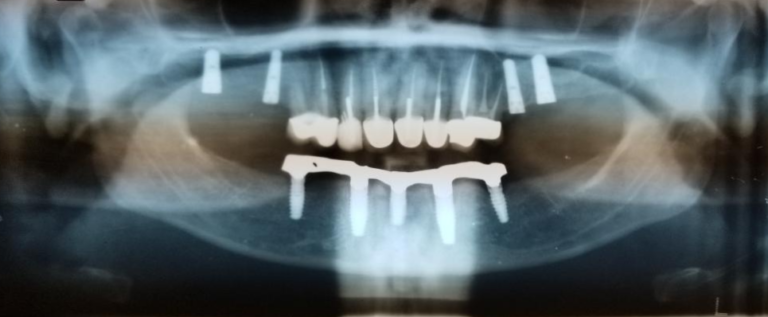

ALL-ON-4 IMPLANTS

All-On-4 implants are an advanced way of replacing missing teeth. This is a minimally invasive procedure that uses four implants to place a full set of implants in your mouth. This procedure supports a full arch and gives you the real and natural look of your original set of teeth.